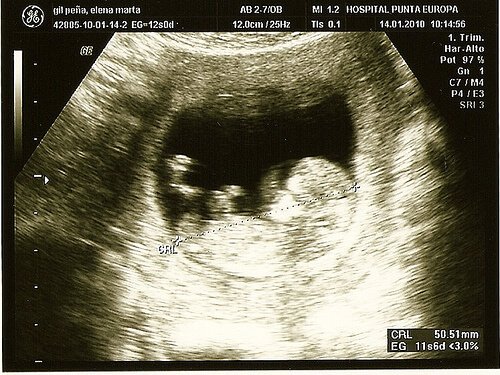

Fosterdiagnostik

Fosterdiagnostik är avgörande för både dig och din bebis för att ni ska kunna gå igenom denna process på bästa sätt. Därför har vi samlat all den här goda informationen för dig gällande medcinska tester och hur du tar hand om dig själv i varje trimester. Varje mamma förtjänar en lycklig och hälsosam graviditet.